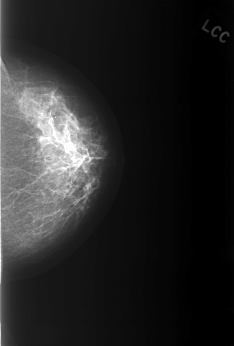

ics_version 1.0 filename C-0365-1 DATE_OF_STUDY 19 8 1996 PATIENT_AGE 52 FILM FILM_TYPE REGULAR DENSITY 2 DATE_DIGITIZED 13 10 1998 DIGITIZER LUMISYS LASER SEQUENCE LEFT_CC LINES 5536 PIXELS_PER_LINE 3744 BITS_PER_PIXEL 12 RESOLUTION 50 NON_OVERLAY LEFT_MLO LINES 5288 PIXELS_PER_LINE 3928 BITS_PER_PIXEL 12 RESOLUTION 50 NON_OVERLAY RIGHT_CC LINES 5624 PIXELS_PER_LINE 3752 BITS_PER_PIXEL 12 RESOLUTION 50 OVERLAY RIGHT_MLO LINES 5584 PIXELS_PER_LINE 3712 BITS_PER_PIXEL 12 RESOLUTION 50 OVERLAY |